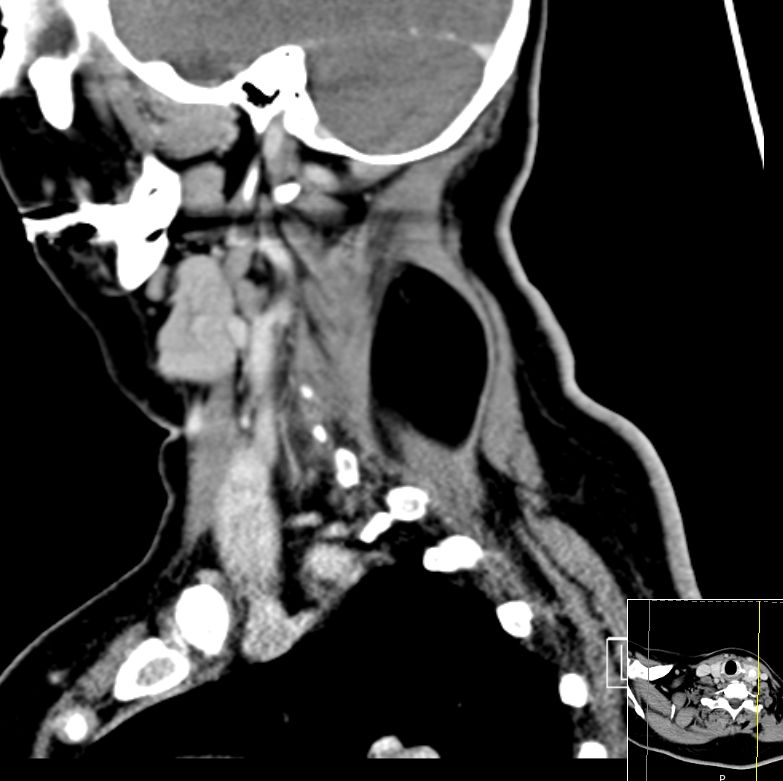

67-jährige Patientin mit einer Raumforderung im Nacken. Das CT zeigt eine fettdichte Struktur innerhalb der dorsalen Halsmuskulatur.